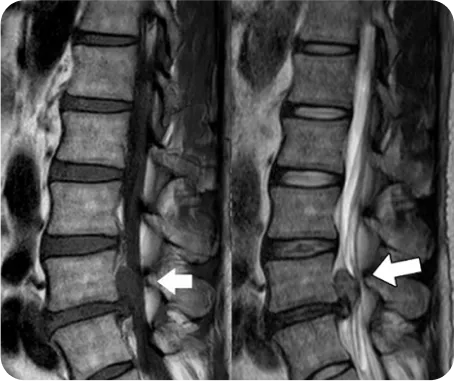

▲ 허리디스크 환자의 MRI

척추 사이 디스크 손상

사고로 인한 충격

그대로 흡수

교통사고 발생

주변의 연부조직 손상

및 신경압박

교통사고 후유증 발생

평소 척추 관절질환이 있는 사람이라면

교통사고의 충격은 일반 사람들에 비해

더 크게 발생하며 해당 질환이

더욱 악화가 될 수 있습니다.